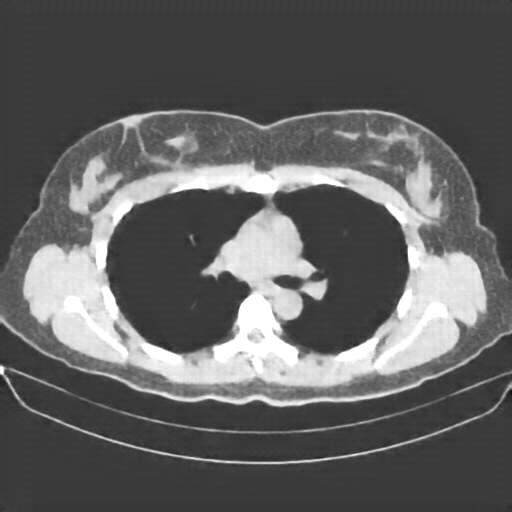

Image Grid

4Γ—3 grid: Rows show different image types (Original NATIVE, Reconstructed NATIVE, Original VENOUS, Generated VENOUS), Columns show windowing techniques (No Window, Lung Window, Mediastinum Window)

Mediastinum window (WL 40, WW 400 β†’ Low βˆ’160, High +240)